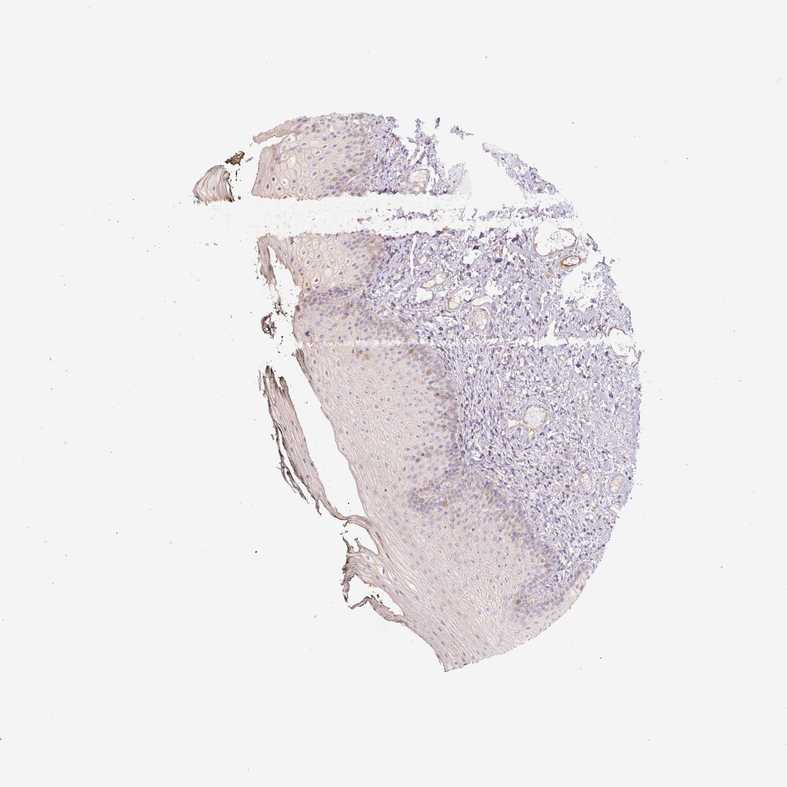

CCNI2